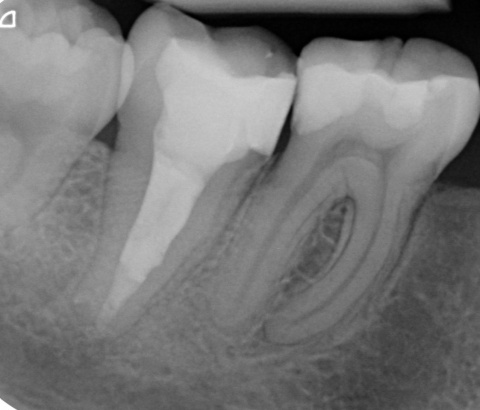

Im ersten Fall stellte sich die Patientin nach bereits erfolgter endodontischer Behandlung an Zahn 47 mit Beschwerden, die insbesondere bei okklusaler Belastung auftraten, vor. Die Provokation mittels Perkussion fiel positiv aus. Das daraufhin angefertigte Röntgenbild (Abb. 1) zeigte eine bis zum Apex reichende Wurzelfüllung mit apikaler Aufhellung und Ausdehnung der Osteolyse bis zum Dach des Nervus alveolaris inferior. Insgesamt war die Wurzelfüllung als inhomogen zu bewerten. Nach Aufklärung über die Therapiealternativen entschied sich die Patientin für einen Revisionsversuch.

Ein nach Applikation des MTA angefertigtes Kontrollbild zeigt den suffizienten apikalen Verschluss der Konstriktion in einer Schichtstärke von etwa vier Millimeter (Abb. 2). Gleichzeitig wird in der Aufnahme die ausgedehnte Kanalstruktur des Zahnes 47 deutlich.